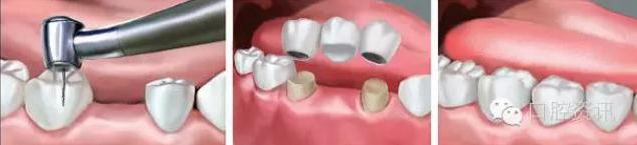

2 . 牙支持式固定義齒

也稱固定橋,是通過固位體與人工牙連接成為一個整體,利用粘結(jié)劑

固定在缺牙間隙兩端或一端的天然牙或牙根上,以修復缺失牙。這類

義齒需要磨切天然牙(有時需要在局部麻醉下完成),但舒適度好,

無需患者自己取戴,功能和美觀恢復較好。

7.jpg

圖7. 固定橋